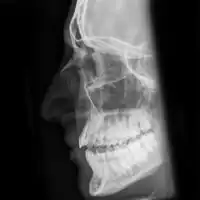

| Plain X-ray showing a nasal fracture | |

The most common causes include assault, trauma during sports, falls, and motor vehicle collisions.[1] Diagnosis is typically based on the signs and symptoms; with plain X-ray rarely of benefit.[1][6] CT scan may be useful if concerns of other fractures or complications are present.[6][4]

Nasal fractures are usually identified visually and through physical examination.[1] Medical imaging is generally not recommended.[1][2] A priority is to distinguish simple fractures limited to the nasal bones (Type 1) from fractures that also involve other facial bones and/or the nasal septum (Types 2 and 3). In simple Type 1 fractures X-Rays supply surprisingly little information beyond clinical examination. However, diagnosis may be confirmed with X-rays or CT scans, and these are required if other facial injuries are suspected.[2]

Minor nasal fractures may be allowed to heal on their own provided there is not significant deformity. Ice and pain medication may be prescribed to ease discomfort during healing.[1] For fractures where the nose has been deformed, manual alignment may be attempted, usually with good results. A CT scan of the facial bones is recommended before this occur.[4] The reduction can take place within the next two weeks and potentially up to 5 weeks; though repair is recommended earlier in children (around 7 days).[4]